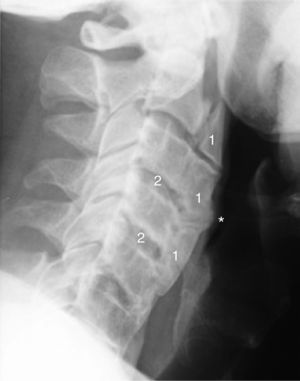

The assessment of the radiological changes in the cervical spine of this patient over a 5-year period revealed an increase in osteophyte size and in the ossification of anterior cervical ligament, which affected several contiguous vertebrae (Figs. 1 and 2). This could explain an extrinsic cause of the dysphagia. There are other radiological features of interest, such as the relative preservation of the intervertebral disc space and the absence of involvement of the facet joints.

Radiography of lateral cervical spine (2014) showing an increase in the extent of ossification of anterior cervical ligament with overall involvement of the cervical spine (1), and a protuberance (*) toward the aerodigestive tract. A relative conservation of the height of the intervertebral disc space is also observed (2).